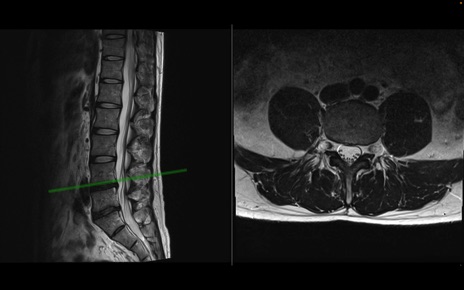

【整形】TIPS症例1 腰椎MRI 横断像と矢状断像

【症例】40歳代男性

【主訴】左臀部〜大腿後面痛み

【現病歴】2週間前から腰痛あり。2日前に夜中にくしゃみをした際に激痛が出現。疼痛強いため来院。

【身体所見】左臀部〜大腿後面、下腿後面のしびれ。SLR -/+ 30度、うつ伏せ困難、筋力低下なし。

異常所見と診断は?